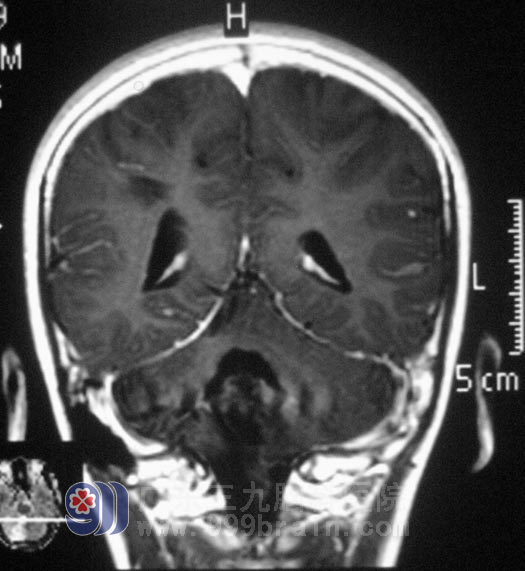

紧急关头,一个杨门女将中的“太君”站出来了,奶奶做出明智的选择——到广州治疗!于是,挎上行李,婆孙俩来到三九脑科医院,找到外科专家鲁明主任,听完了老人家对小海病情的描述,鲁明主任被老人家这种深明大义的精神感动,指示一定尽全力治疗小海。经过缜密的讨论,第一步,给小海行脑室腹腔分流术,解除脑积水症状,待恢复后,在全麻下行右侧小脑半球肿瘤切除术,术中见肿瘤质软、色黄,在显微镜下予肿瘤切除,手术过程顺利,术后小海清醒后未诉不适,经过住院治疗,小海头不痛了,走路不再像喝醉酒似的,又恢复了以前天真乖巧的样子了,小海的奶奶对鲁明主任的手术治疗表示非常满意。术后经病理证实为:(右侧小脑)毛细胞型星形细胞瘤,WHO I级。http://www.999brain.com/

术后